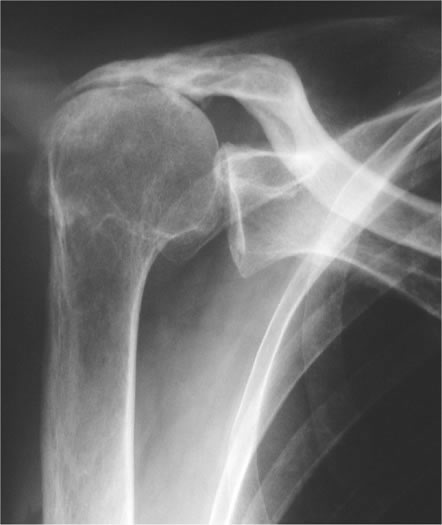

Behandlungen von Schulter-, Ellbogen- und Handgelenks-verletzungen sind oft sehr anspruchsvoll und komplex. Deshalb ist mit einer längeren Erholungsphase in vielen Fällen bis zu 6 Monaten und länger zu rechnen, beispielsweise bei Operationen bei Schulterluxationen und Instabilitäten am Schultergelenk, Schultergelenksarthroskopien bei Einklemmungssyndromen, Rekonstruktion der Rotatorenmanschette, Kunstgelenk-ersatzoperationen an der Schulter. Die Entwicklungen auf diesem Fachgebiet sind enorm vorangeschritten, sodass heute viele Eingriffe in entsprechender arthroskopischer oder minimal-invasiver Technik durchgeführt werden können. Dies führt in der Regel zu bedeutend kürzeren Spitalaufenthalten und schnellerer Erholung.

Die  wichtigsten Verletzungen und Erkrankungen an Schulter, Ellbogen und Hand: